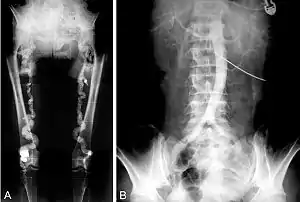

- تصلب شرايين مونكيبيرغ أو التصلب التكلسي المتوسط يحدث غالبًا في كبار السن، في شرايين الأطراف عادة.[8]